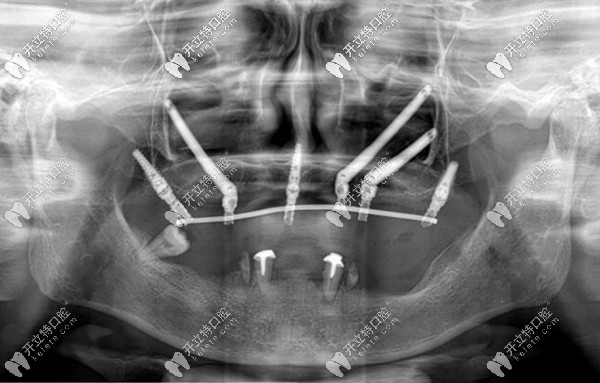

穿顴穿翼種植體在面部骨骼的分布圖

對(duì)于上頜骨極度缺失,行雙側(cè)上頜竇提升術(shù)和植骨術(shù),均為能有效成骨的缺牙病例,做常規(guī)種植肯定是行不通的,此時(shí),高難度的穿顴穿翼種植牙則是較好的修復(fù)方法。

但是,難度高,也就代表著手術(shù)的復(fù)雜程度高,稍有不慎,將會(huì)出現(xiàn)不可逆的危害和并發(fā)癥。以下就是穿顴穿翼種植牙的風(fēng)險(xiǎn):